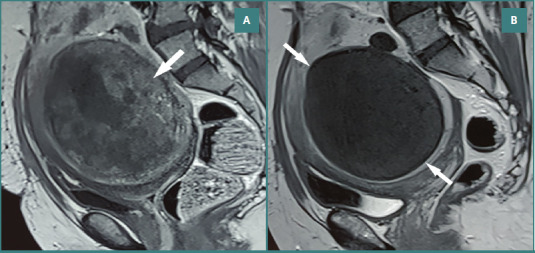

本研究的目的是比较使用非球形聚乙烯醇颗粒(nsPVA)或三丙烯-明胶微球(TAGM)子宫动脉栓塞(UAE)后盆腔MRI的平滑肌瘤梗死率和栓塞成功率。回顾性分析141例(平均年龄38岁)接受标准双侧UAE合并nsPVA (n = 80)或TAGM (n = 61)的患者。栓塞成功的定义是所有可识别的肌瘤完全梗死。采用Mann-Whitney U检验和独立样本t检验比较数据类型。进行二元逻辑回归。556个肌瘤被评估,子宫中位体积为435 cm3,优势肌瘤中位体积为110 cm3。两组患者的基线特征包括年龄(P = 0.446)、子宫体积(P = 0.148)、显性肌瘤体积(P = 0.124)和非梗死性肌瘤数量(P = 0.092),差异无统计学意义。nsPVA组和TAGM组的肿瘤梗死率分别为74%(251/337)和79%(174/219),两者基本相似(P = 0.191)。同样,两组的栓塞成功率相似(nsPVA和TAGM分别为67.5%和72.1%,P = 0.589)。初步非梗死肌瘤数量与栓塞成功率呈负相关(P = 0.035)。本研究评估了这两种物质的可用性和副作用,并对患者进行了6个月的MRI随访,以评估可能的后果。根据栓塞后的MRI, nsPVA和TAGM的平滑肌瘤梗死和栓塞成功率相似。子宫和肌瘤体积的减少与两种药物相似。

The aim of this study was to compare leiomyoma infarction rates and embolization success using pelvic MRI following uterine artery embolization (UAE) using non-spherical polyvinyl-alcohol particles (nsPVA) or tris-acryl-gelatin microspheres (TAGM). A retrospective analysis was performed in 141 patients (mean age, 38 years) who underwent standard bilateral UAE with either nsPVA (n = 80) or TAGM (n = 61). Embolization success was defined as complete infarction of all discernible fibroids. Mann-Whitney U and independent-sample t-test were used to compare data types. A binary logistic regression was performed. 556 fibroids were evaluated, with a median uterine volume of 435 cm3 and a median dominant fibroid volume of 110 cm3. There were no significant differences between the two groups regarding baseline characteristics, including age (P = 0.446), uterine volume (P = 0.148), dominant myoma volume (P = 0.124), and non-infarcted myoma number (P = 0.092). The tumor infarction rate in the nsPVA and TAGM groups was 74% (251/337) and 79% (174/219), respectively, which was approximately similar (P = 0.191). Likewise, embolization success was similar among both groups (67.5% vs. 72.1% for nsPVA and TAGM, respectively, P = 0.589). There was an inverse relationship between the number of preliminary non-infarcted myomas and embolization success rate (P = 0.035). This study assessed the availability and side effects of these two substances, and patients underwent a 6-month follow-up MRI to evaluate possible consequences. According to post-embolization MRI, the leiomyoma infarction and embolization success rates for nsPVA and TAGM were similar. The decrease in uterine and myoma volumes was analogous to both drugs.